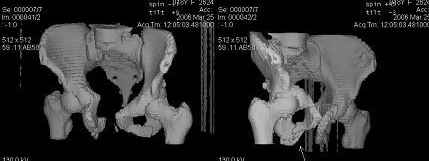

Уважаемые коллеги! Девушка 18л сросшиеся переломы лонных, седалищных костей с обеих сторон, перелом крестца справа,перелом костей голени справа (зио), 3 мес после травмы, АВФ снят с таза.

Патологической подвижности нет. Стоит самостоятельно, ходит с костылями, поскольку 3 месяца практически не ходила. Беспокоит выступание лонной кости в области лобка, хотя объективно грубого косметического дефекта нет. На кт разворот лонной кости в сагиттальную плоскость. Вопрос: стоит ли добиватьсяполной репозиции или же достаточно произвести остеотомию верхушки выступающего отломка?

Предварительный диагноз- посттравматическая вертикальная нестабильная деформация таза II степени, неправильно срастающийся перелом боковой

массы крестца справа, правой лонной и седалищной костей, застарелый разрыв лонного сочленения.

Для уточнения диагноза ниеобходимы обзорные рентгенограммы таза (прямая и inlet), Кт срезы на уровне переломов для определения степени сращения и решения вопроса о методе оперативного восстановления анатомии (делать ли остеотомию, низводить ли задние отделы), ни о какой "остеотомии выступающих отломков" тем более у девочки 18 лет речи быть не может.

Предоставляю срезы. Если пациентку функционально ничего не беспокоит, стоит ли навязывать ей лечение.